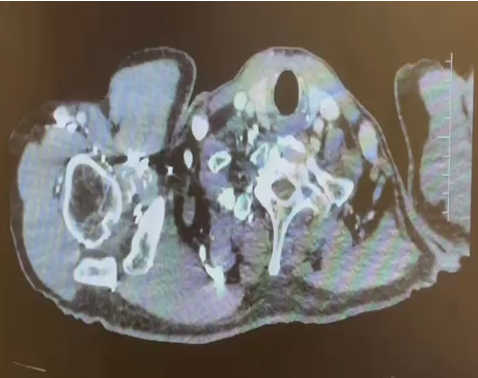

主诉:活动后气促 1 月余,检查发现右肾肿瘤并腔静脉 II 级瘤栓。

2024.1检查报告

CT检查报告 | 1.左肺动脉主干及分支、右下肺动脉分支多发肺栓塞; 2.下腔静脉、右肾静脉及其属支、左肾静脉及左侧髂总静脉多发血检形成,请结合临床。 3.双肺散在炎症,双侧胸膜增厚; 4.右肾大片状低强化灶,请结合临床。 | 日期 | 2024.1.10 |

CT检查报告 | 1.左肺动脉主干及分支多发肺栓塞较前范围扩大,右上肺后段动脉、右中肺外侧段动脉内肺栓塞,右下肺动脉分支内肺栓塞较前稍吸收减少; 2.右肾静脉及其属支充盈缺损较前相仿,左肾静脉充盈缺损较前范围缩小,下腔静脉、左侧髂总静脉内多发充盈缺损较前范围扩大; 3.双肺散在炎症较前減少,双侧胸膜增厚; 4.左肺上叶尖后段磨玻璃结节,性质待定 建议复查; 5.右肾大片状低强化灶,请结合临床。 | 2024.1.22 |

CT平扫+增强

检查诊断:

1.下腔静脉管腔较前缩小、充盈缺损较前略减少;

2.右肾静脉栓子同前;左肾静脉充盈缺损未见显示;双侧骼静脉充盈欠佳;

3.右肾上极病变同前:恶性肿瘤可能;右肾盂管壁增厚强化:受累?

4.盆腔少量积液;

5.右肝动脉起自肠系膜上动脉;左下肺动脉栓子;

日期:2024.3.3